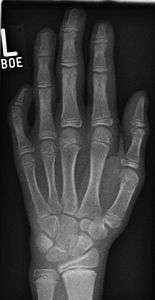

Radiograph showing clinodactyly

| The picture above illustrates a moderately severe case of this condition. | |